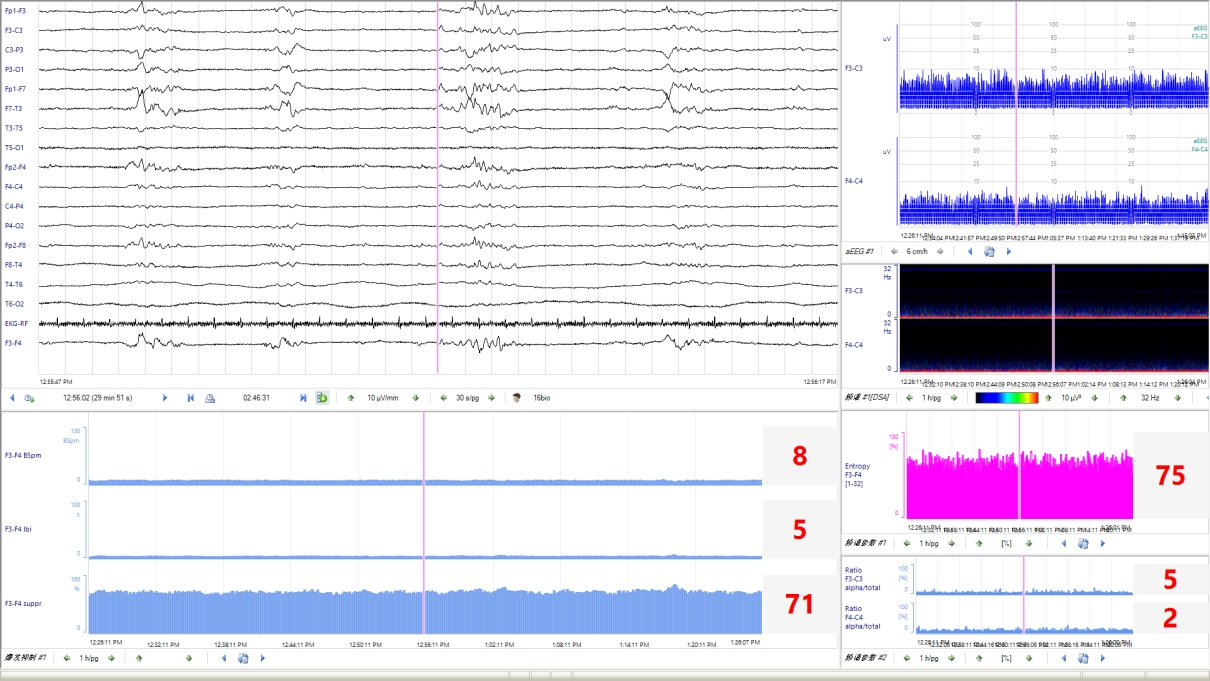

Q3:新生兒 aEEG的評價標準是什么?aEEG 主要從背景活動、睡眠周期及驚厥三方面進行評價和分類。aEEG的連續性亦被臨床廣泛關注。

睡眠周期未達到相應PMA成熟度的表現,則為睡眠周期落后于胎齡。3、驚厥發作(1) 單次發作:aEEG波譜帶短暫中斷,呈“駝峰”、“城垛”、“拱形”、“缺口”樣改變。(2) 反復發作:aEEG出現多次上述改變。(3) 驚持續狀態:既往認為發作時間超過30min或腦電圖監測過程中異常放電占總監測時間的50%以上為驚持續狀態。然而,為了減少驚厥發作時間及可能造成的神經損傷,aEEG表現為“鋸齒”樣波形時,即可根據不同的發作形式,在更短的時間窗內做出臨床治療決策。在KCNQ2基因致病性變異所致的發育及癲癇性腦病中,發作期aEEG呈現短暫上升后急劇下降(倒駝峰狀)表現,aEEG中的短暫上升圖形對應原始腦電圖的發作期圖形,急劇下降圖形對應原始腦電圖發作期后的廣泛性電壓衰減、甚至抑制圖形。4、總體評估綜上,近足月兒和足月兒可綜合aEEG的背景活動、睡眠周期及有無驚厥進行總體評估,分為正常、輕度異常和重度異常,aEEG異常提示患兒可能存在腦損傷或腦發育成熟度延遲。Q4:早產兒 aEEG的特點及其臨床意義?早產兒aEEG的背景活動、睡眠周期隨胎齡而變化。隨胎齡的增加,振幅上邊界逐漸降低,下邊界逐漸升高;睡眠周期也從最早的無法辨認到出現成熟的正弦樣變化;aEEG圖形由不連續圖形過渡為連續圖形。見表1。通過aEEG圖形變化可定性評價早產兒的腦發育情況。

Q5:aEEG診斷新生兒腦病及判斷神經發育預后的價值?aEEG可用于輔助診斷出生后6h內缺氧缺血性腦病(hypoxic-ischemic encephalopathy,HIE)的嚴重程度。窒息新生兒出生后6h內aEEG背景活動異常可作為開始亞低溫治療的準入標準,建議至少監測30min。但是不能因aEEG背景活動正常將HIE新生兒排除在亞低溫治療之外,需進一步結合臨床。建議在新生兒HIE亞低溫治療和復溫期間進行連續aEEG監測,或者每天監測一次、每次至少2h,以評價腦功能和疾病轉歸。aEEG對預測HIE新生兒預后具有一定的敏感性和特異性,應重點關注aEEG背景活動及其動態變化趨勢。行亞低溫治療的患兒,48h aEEG的背景活動和睡眠周期很關鍵,治療48h后aEEG正常的患兒預后好。復溫時無睡眠周期與預后不良相關未行/無條件行亞低溫治療的患兒,6h aEEG正常的患兒神經發育預后好;36h有睡眠周期的患兒神經發育預后好。持續的背景活動異常和缺乏睡眠周期與2歲時發育遲滯相關。代謝性腦病患兒中,70% aEEG背景活動異常,60%出現癲癇發作。Q6:如何應用aEEG篩查和準確識別新生兒驚厥?新生兒驚厥的臨床表現不典型,部分驚厥可只有電發作而無臨床表現,故可能因漏診而延誤治療,從而引起或加重腦損傷。另外,部分抗驚厥發作藥物有潛在的神經毒性。故通過持續的床旁腦電監測,可以減少漏診、避免過度診斷,并指導抗驚厥發作藥物的精準使用。aEEG對驚厥監測的優點是時效性強,可以直接、快速地在床旁開展,且可長時間監測,常用于新生兒驚厥的篩查、療效監測和評估。但由于aEEG為時間壓縮圖形,可能會漏掉振幅低、發作時間短(<30s)和起始部位距離監測電極遠的驚厥。缺乏發作期腦電圖的時空演變圖形(通常在多通道腦電圖中可以看到)是aEEG的另一個重要限制,如結合有視頻記錄的原始腦電圖,aEEG對于驚判讀的敏感度和特異度可分別達到76%和85%左右。早產兒驚厥的診斷在臨床上更為棘手,由于早產兒驚厥時臨床癥狀相對不明顯或不典型,發作期腦電活動持續時間相對短,振幅低,擴散范圍小,發作期的aEEG圖形常不易識別;新生兒重癥監護室中呼吸機的使用和各類操作干擾也可造成疑似驚厥發作圖形而誤診。因此aEEG中出現任何可疑的上下邊界短暫改變時,均需通過對比同期的原始腦電圖加以證實。視頻腦電圖(video-electrencephalography,VEEG)是新生兒驚厥診斷的金標準。沒有多導VEEG的前提下,aEEG可以用于新生兒驚厥發作的監測,但是需要同時分析原始腦電圖,最大限度避免偽差干擾導致的誤診。當臨床高度懷疑有驚厥發作而aEEG未監測到癇性放電時,建議增加導聯數量,使用8導以上帶有視頻監測的aEEG設備。有條件的醫院應進行長程vEEG監測。使用aEEG進行新生兒驚厥診斷時,建議至少有一次vEEG檢查,并與神經電生理專家密切合作。